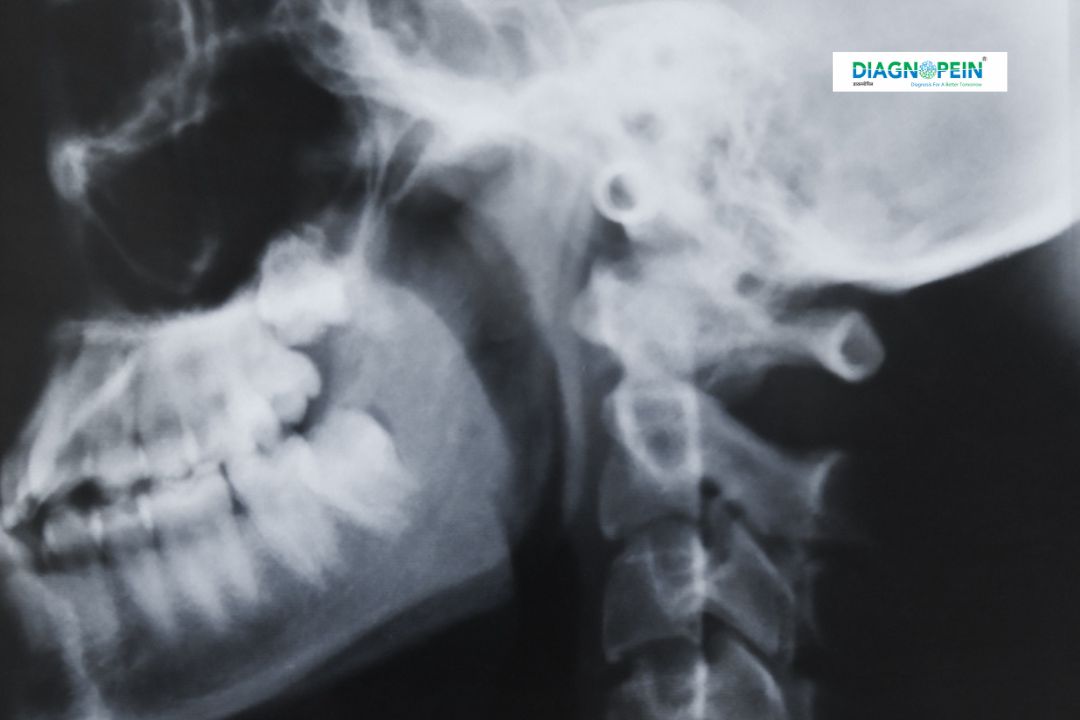

X-Ray Skull Lateral is a specialized radiographic imaging technique used to capture a side view of the skull. This diagnostic test helps doctors evaluate the bones of the skull, cranial structure, facial bones, and sinus regions with clarity. The lateral skull view is commonly prescribed to detect fractures, deformities, abnormal bone growth, sinus issues, and certain neurological conditions.

At Diagnopein, X-Ray Skull Lateral in Nashik is performed using advanced digital X-ray systems that ensure high-resolution images with minimal radiation exposure. This test plays an important role in early diagnosis and accurate treatment planning for head-related conditions.

During the procedure, the patient is asked to stand or sit beside the X-ray machine. The head is positioned sideways so that one side of the skull faces the detector. The radiology technician ensures proper alignment to capture a precise lateral view. Patients are advised to remain still for a few seconds while the image is taken.